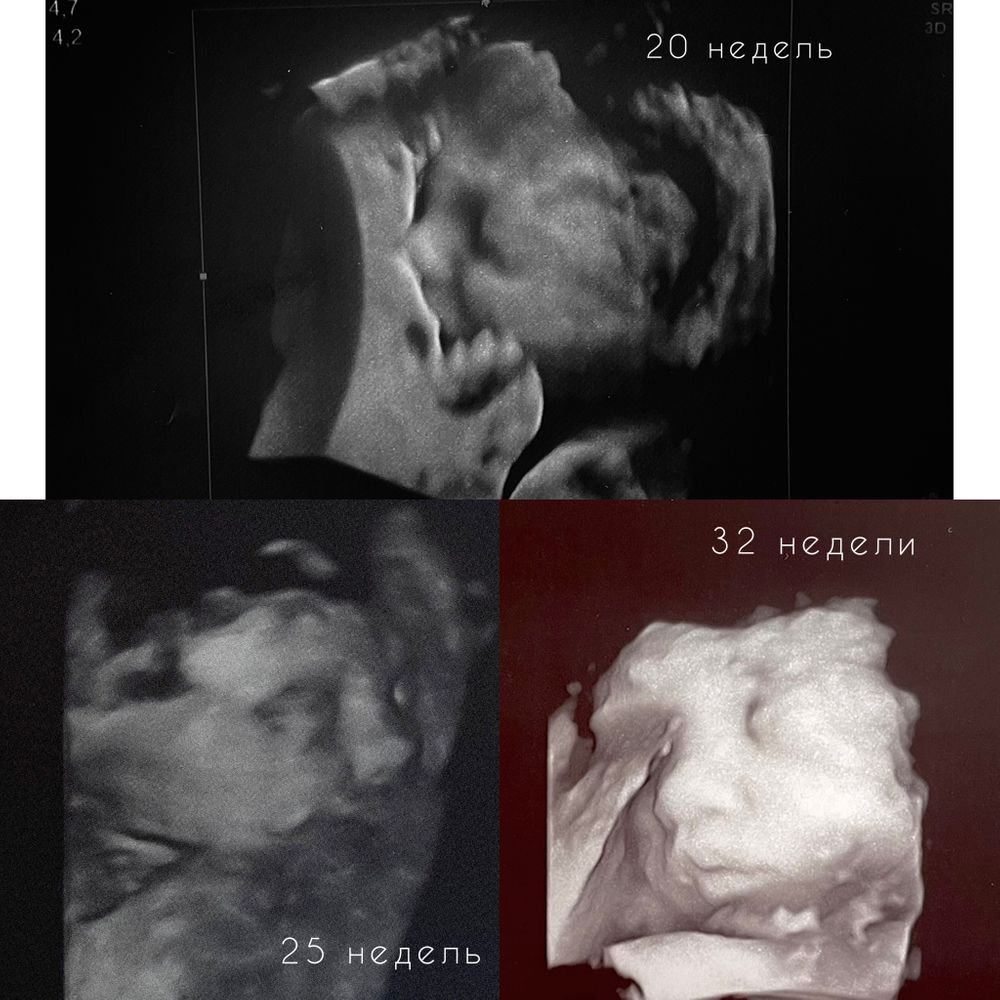

УЗИ, КТГ, доплерДевочки посоветуйте пожалуйста на каком сроке лучше делать 4 Д узи, с целью посмотреть на малыша чтоб запечатлить моменты, и малыш чтоб уже был похож на ребёнка😃 записалась на узи в 27 недель ровно но думаю не рано ли

Мне врач узист на 2 скрининге сказала, оптимальное время для 3д-4д это 27-30 недель. Но тут как повезёт, у нас были руки у лица и уткнулась носом в плаценту, поэтому особо не получилось 3д

Думаю будет хорошо, т.к после 30 недель уже не возможно полностью охватить лицо чётко,т.к ребенок уже большой. А так я 2 разв была и у нас нет нормального фото))В первый раз прикрывали руками , потом вообще отвернулись.Во второй раз лицом уткнулись и спали.Кстати после рождения тоже любили спать на животе))

Да, лучше после 30 недель. Я В 31 неделю делала. Дочь прям похожа на себя, когда родилась)